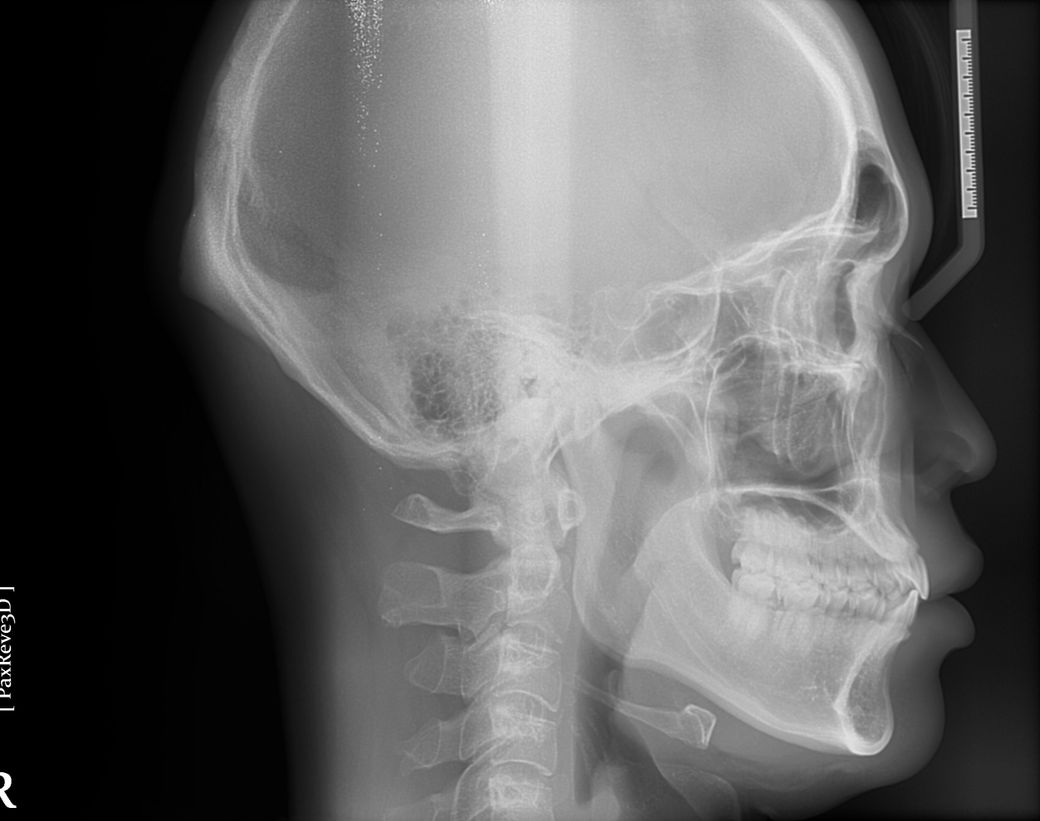

제 옆모습을 가끔 보면 턱이랑 입이 나온것같아보이는데 전문의가 평가하기에도 그런지 알고싶어요

가끔 사진찍히거나 거울볼때 옆모습이 입이랑 턱이 남들보다 나온것같다는 생각이들거든요 이런게 주걱턱인가? 이게 치과에 문의하는게 맞는지 모르겠지만 전문의님 개인평가를 듣고싶어요~ 나중에 구강악쪽 양악수술 상담한번 받아보려고요

하악골이 살짝 전방돌출되어있는 양상이나 치아의 교합이 좋은 상황이므로 교정이나 수술적 처치가 반드시 필요한지 의문입니다.

1. 골격적으로 3급으로 보여집니다. 즉 하악이 발달한 상태이며 따라서 안모적으로 입이나 턱이 나와 보일 수 있습니다.

안모자체가 약간 입술이 튀어나와보이긴 하나, 자세히 보지 않는다면 거의 느끼지 못할 정도입니다.